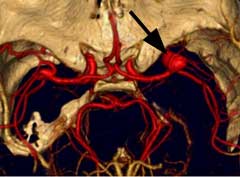

顱內動脈瘤2.因顱內動脈瘤多位於顱底部WiLLis動脈環,直徑小於1.0C的動脈瘤,CT不易查出。直徑大於1.0cm,注射對比劑後,CT掃描可檢出。MRI憂於CT,動脈瘤內可見流空。MRA可提示不同部位動脈瘤,常用於顱內動脈瘤篩選。三維CT(3D—CT)從不同角度了解動脈瘤與載瘤動脈的關係,為手術夾閉動脈瘤決策提供更多的資料。

3.腦血管造影是確診顱內動脈瘤必須的檢查方法,對判明動脈瘤的準確位置、形態、內徑、數目、血管痙攣和確定手術方案都十分重要。DSA更為清晰。,經股動脈插管全腦血管造影,可避免遺漏多發動脈瘤。病情在三級以下,腦血管造影應及早進行,三級和三級以上病人可待病情穩定後,再行造影檢查。及早造影明確診斷,儘快手術夾閉動脈瘤,可以防止動脈瘤再次破裂出血。首次造影陰性,可能因腦血管痙攣而動脈瘤未顯影,高度懷疑動脈瘤者,應在3個月後重複造影。

(1)以出血為首發征像時,臨床懷疑動脈瘤而行血管成像(DSA、CTA、MRA)可證實動脈瘤的存在,一般無需鑑別,但應注意假陽性和假陰性的存在。假陽性如頸內動脈起始部、後交通動脈起始部漏斗樣增粗如正常現象,血管轉折處在MRA上易誤為異常,兩段狹窄間正常管腔易誤為動脈瘤等。假陰性如動脈瘤破裂或痙攣導致造影時不能顯示等。這方面CTA較DSA和MRA有明顯優勢,它可以對單枝血管進行曲面重建並鏇轉觀察,有利於分析動脈壁的結構是否正常,有利於發現無造影劑充盈的瘤體等。